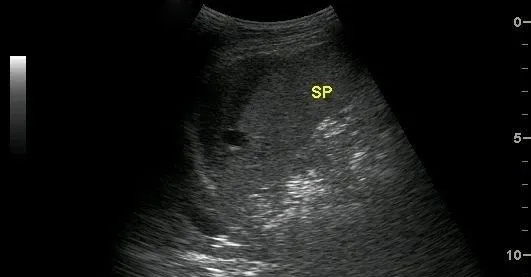

超聲表現(xiàn)為:脾臟實質(zhì)內(nèi)探及邊界清楚的非均質(zhì)區(qū),單發(fā)或多發(fā),如伴有較大血腫時,非均質(zhì)區(qū)內(nèi)可探及不規(guī)則或類圓形無回聲區(qū),透聲較差。

真性脾破裂

是指脾臟實質(zhì)及包膜同時破裂,導(dǎo)致腹腔內(nèi)大出血,可短期內(nèi)造成患者失血性休克。

超聲表現(xiàn)為:脾包膜連續(xù)性中斷,局部回聲模糊,脾內(nèi)見自實質(zhì)延伸至脾臟表面的實性非均質(zhì)區(qū)及無回聲區(qū),腹腔內(nèi)出現(xiàn)大量游離無回聲區(qū)(積血)。